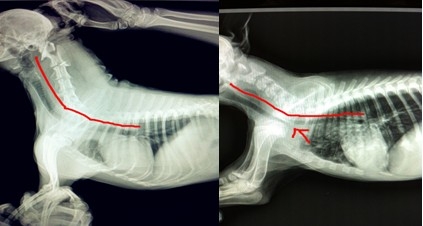

如果您的愛犬依然還是不愿出門,走路會(huì)停下休息,那么請(qǐng)仔細(xì)往下看。如果您的愛犬還小,雖然喜歡在夏天出門,但是半途會(huì)趴下休息,或者喘氣比其他小狗要時(shí)間久,那么很有可能是我們說的第一類潛在疾病!氣管類疾病!由于是不種品種的犬種身體結(jié)構(gòu)特征不同,患此類疾病極有品種傾向,常見的有京巴犬,博美犬,吉娃娃犬,斗牛犬,特別是各種品種犬的迷你種,這些犬類常有前天性的氣管疾病,比如氣管狹窄,氣管塌陷。這些小狗平時(shí)的表現(xiàn)常有有喜靜不喜動(dòng),即使是3歲以內(nèi)的精力旺盛的年輕犬他們好像也不喜歡奔跑,激動(dòng)時(shí)有類似人類哮喘的病狀,但是安靜一段時(shí)間以后就會(huì)好了,如果是這樣的話,請(qǐng)你帶上你的愛犬去醫(yī)院就診,可以照個(gè)X光片,醫(yī)生會(huì)發(fā)現(xiàn)問題的所在。雖然平時(shí)這類疾病不會(huì)影響您愛犬的生活,但是建議您應(yīng)該減少夏天的遛狗時(shí)間,減少您愛犬的不適。

X光數(shù)碼片